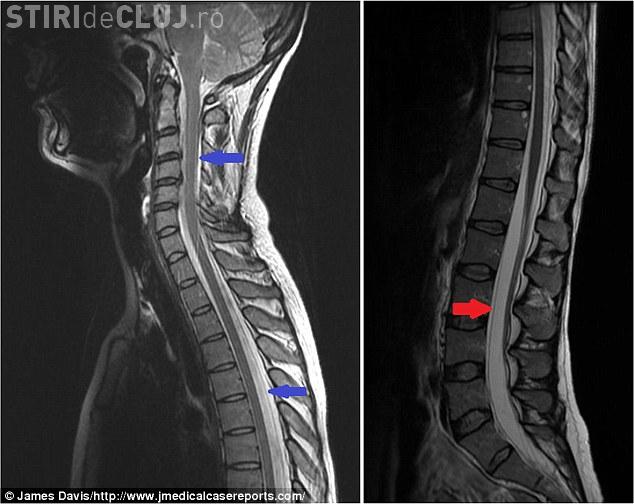

După ce i-au făcut un computer tomograf, medicii au stabilit că lichidul care se află în jurul creierului și a coloanei se scurgea printr-o ruptură musculară.